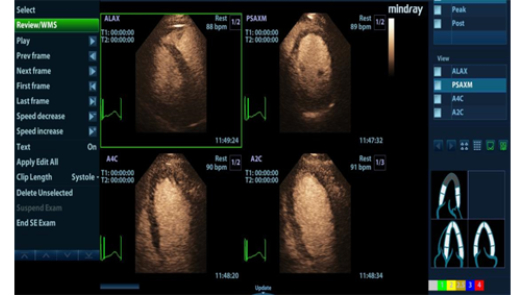

???? ???? ??

? 3?? ???? ????? ?? ???? ?? ??

? ?? ??? ???, ??? ???? ?? ??? ?? ??